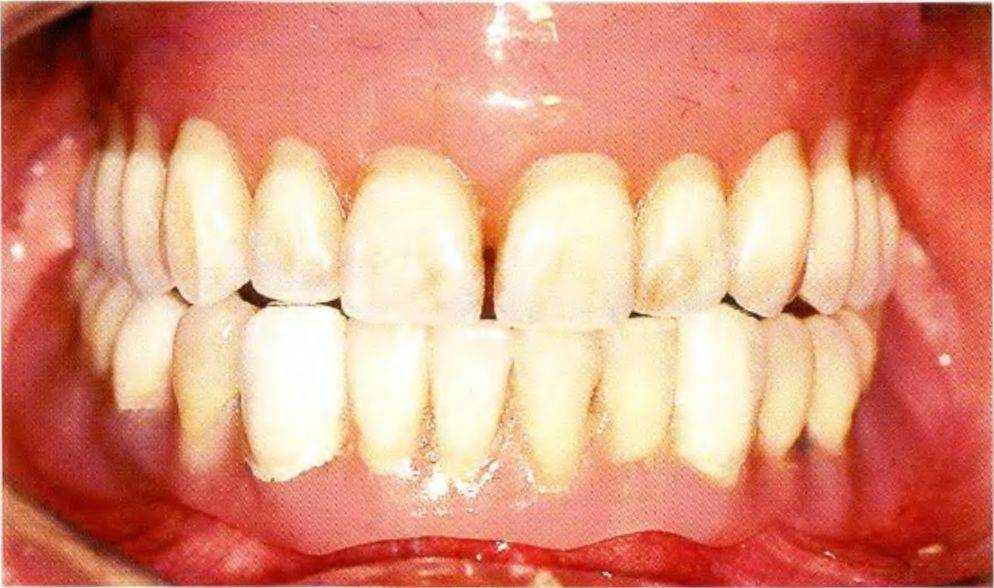

При осмотре определили выраженную атрофию альвеолярных гребней верхней и нижней челюсти, а также сниженную саливацию. Съемные протезы были несостоятельны (рис. 1 -9с). В связи с анамнезом и данными осмотра возникло несколько вопросов:.

Рис. 1-9Ь. Для обеспечения устойчивости протезов пациент вынужден стискивать зубы

Рис. 1-9а. Попытки улыбнуться вызывают у пациента боль, кроме того, ему приходится стабилизировать положение съемного протеза языком.

Рис. 1-9с. Плохоприпасованная пара съемных полных протезов